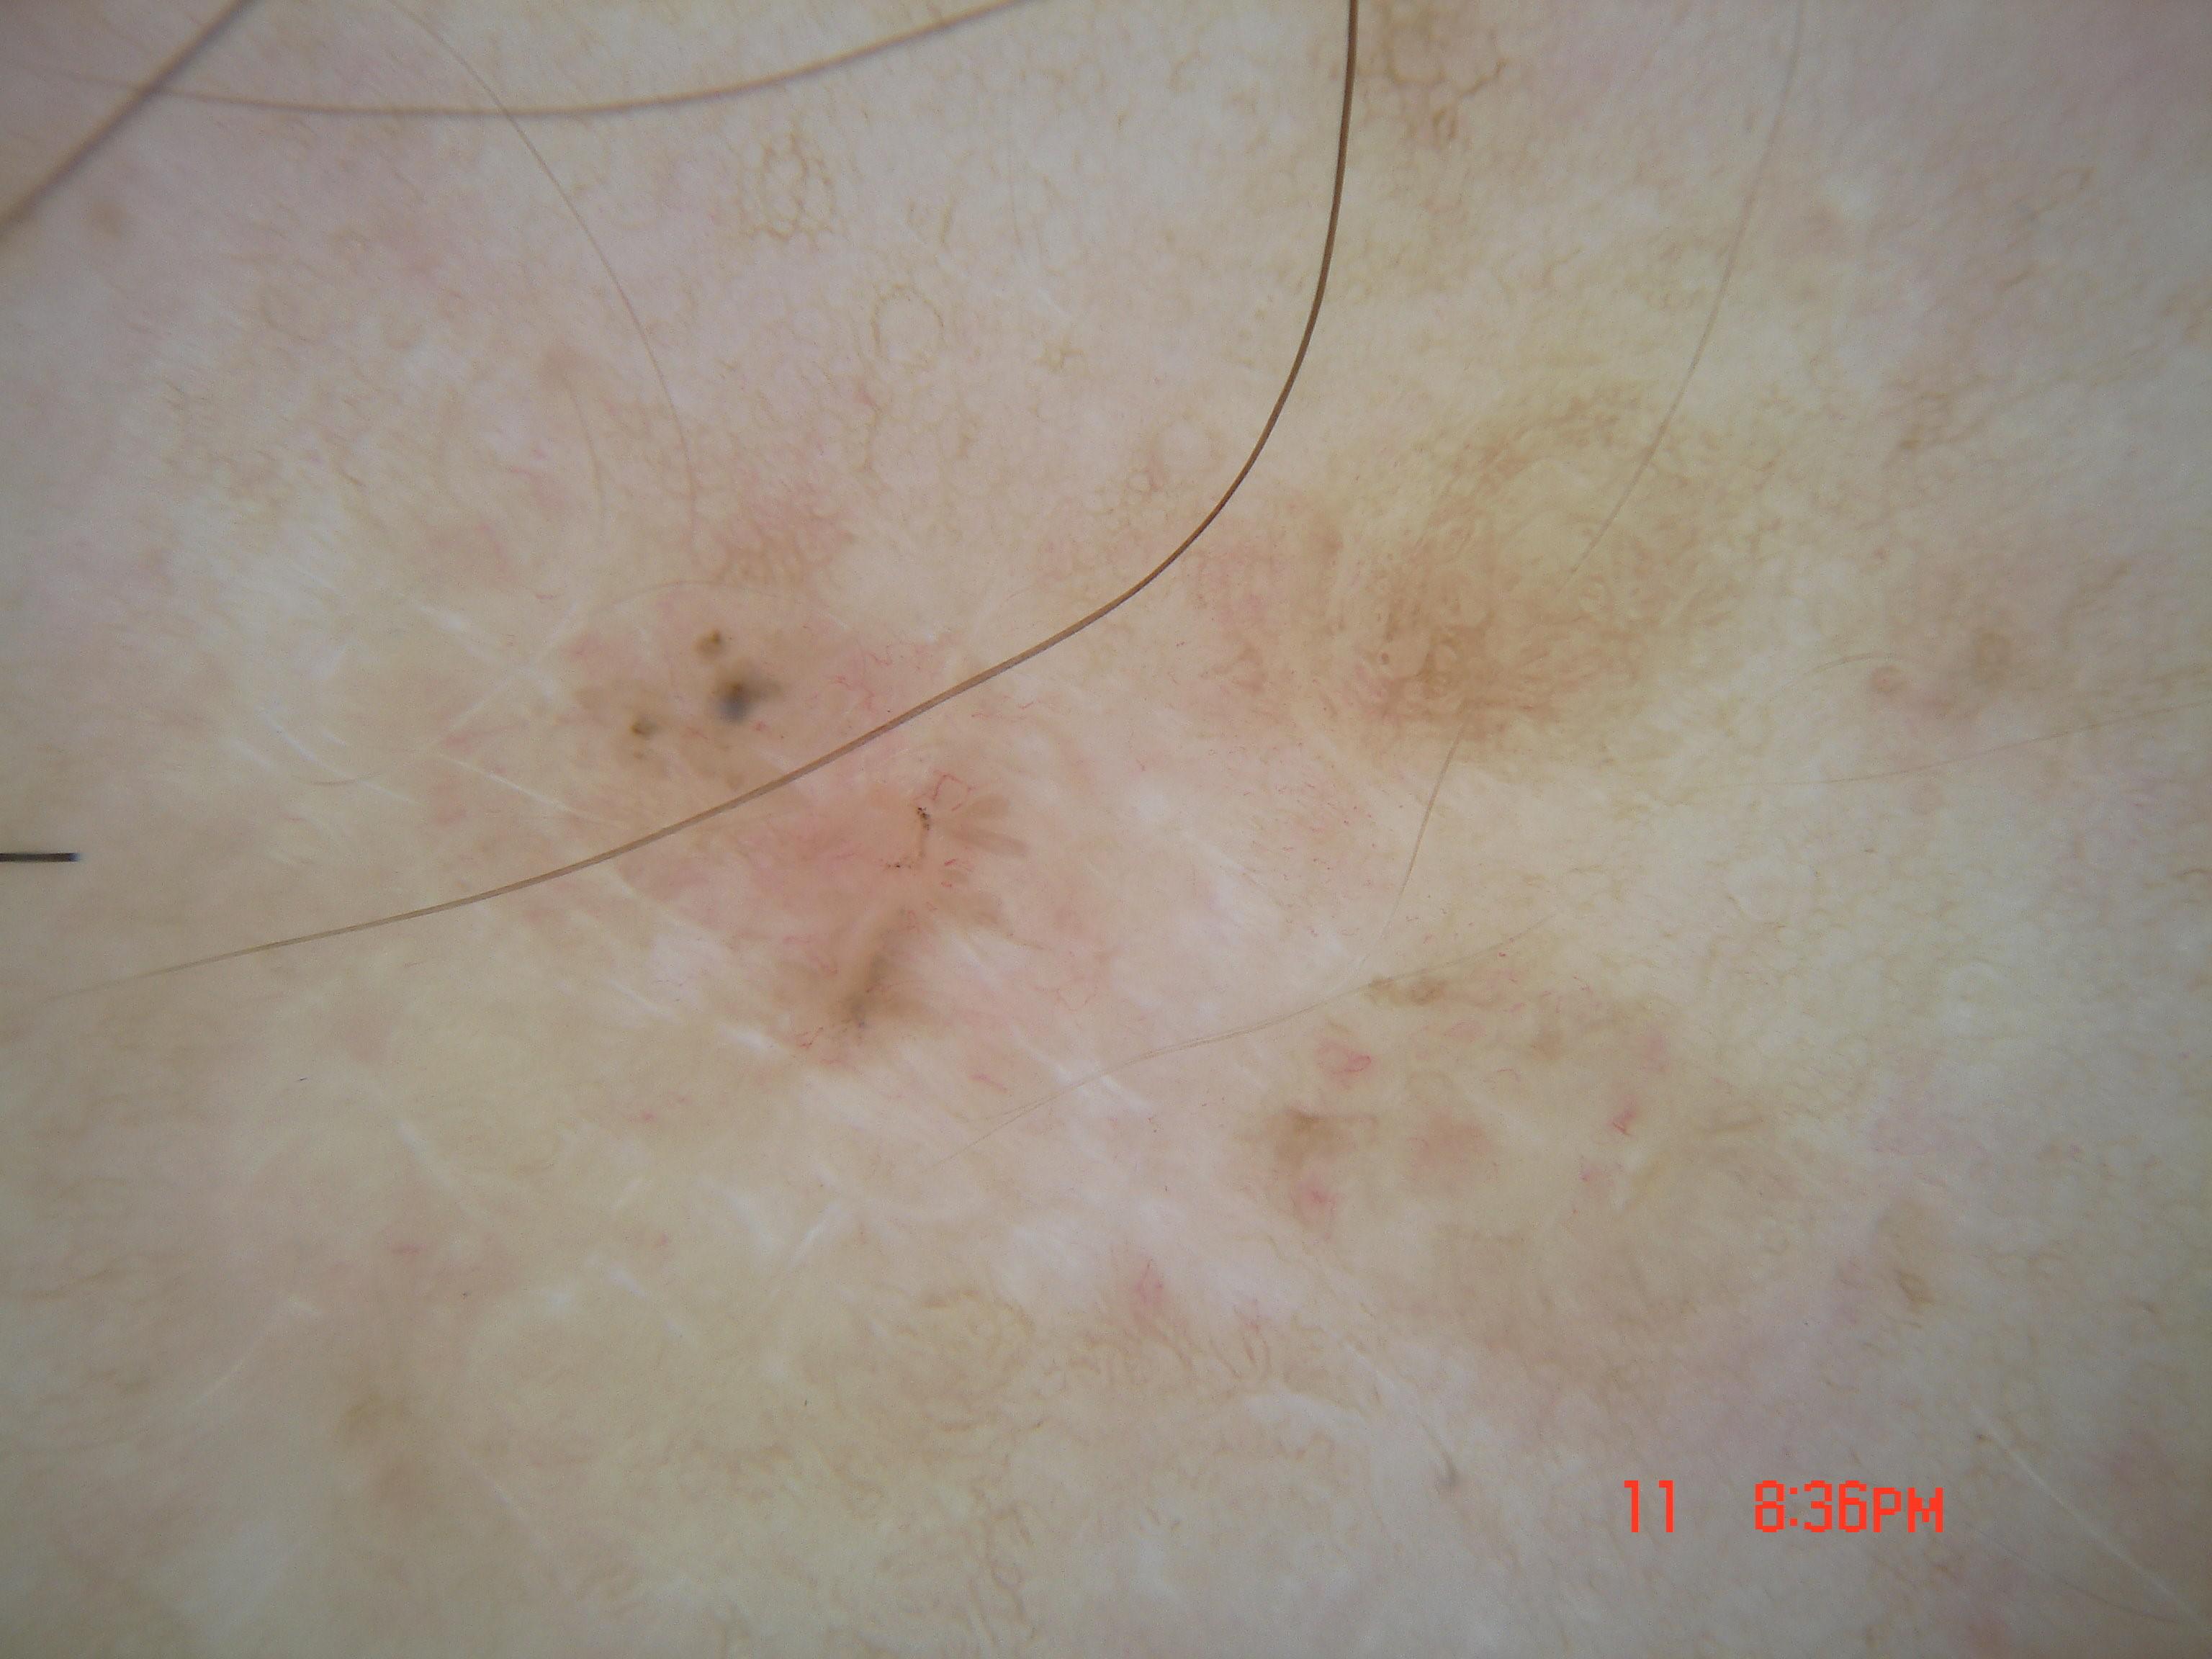

{

"age_approx": 25,

"anatom_site_general": "posterior torso",

"concomitant_biopsy": true,

"dermoscopic_type": "contact non-polarized",

"diagnosis_1": "Benign",

"diagnosis_2": "Benign melanocytic proliferations",

"diagnosis_3": "Nevus",

"diagnosis_4": "Nevus, Atypical, Dysplastic, or Clark",

"diagnosis_5": "Nevus, Clark",

"diagnosis_confirm_type": "histopathology",

"family_hx_mm": false,

"image_type": "dermoscopic",

"melanocytic": true,

"patient_id": "IP_9318788",

"personal_hx_mm": false,

"sex": "female"

}